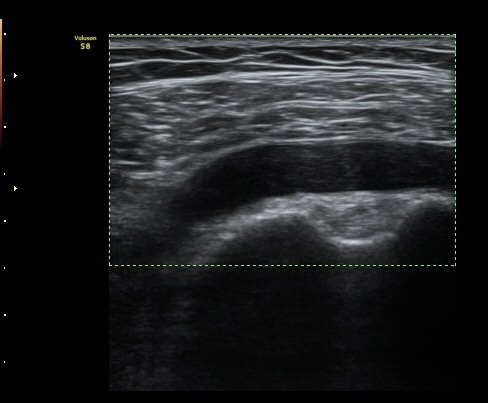

°üÀý³» ¼ö¾×Àú·ù´Â ¶Ñ·ÈÇÏÁö ¾Ê´Ù(±×¸² 3). ±Ø»ó°Ç Á¾´Ü¸é°Ë»ç¿¡¼­ Á¡¾×³¶³» ¼ö¾×

Àú·ù°¡ °üÂûµÈ´Ù(±×¸² 4, 5). ±Ø»ó°Ç Ⱦ´Ü¸é À­ ºÎºÐ¿¡¼­ °æ¹ÌÇÑ ¼ö¾×Àú·ù¸¦ º¸ÀδÙ(±×¸² 6).